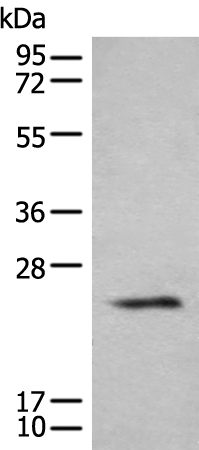

分类: 科研抗体货号: P06279别名:应用: WB,IHC反应种属: Human, Mouse, Rat

分类: 科研抗体货号: P06217别名: NEM7应用: WB,IHC反应种属: Human, Mouse, Rat

分类: 科研抗体货号: P06266别名: NCBP; Sto1; CBP80应用: WB,IHC反应种属: Human, Mouse, Rat

分类: 科研抗体货号: P06210别名:应用: WB,IHC反应种属: Human, Mouse, Rat

分类: 科研抗体货号: P06263别名: CML3; NACED; NAT8-LIKE应用: WB,IHC反应种属: Human, Mouse, Rat

分类: 科研抗体货号: P06205别名: CACC; GOB5; CACC1; CLCRG1; CaCC-1; hCLCA1; hCaCC-1应用: IHC反应种属: Human

分类: 科研抗体货号: P06262别名: DNAS1L2应用: IHC反应种属: Human, Mouse

分类: 科研抗体货号: P06203别名: BHLHF42应用: WB反应种属: Human, Mouse

分类: 科研抗体货号: P06202别名: AMY; CLAC; CLACP; CFEOM5; CLAC-P应用: WB,IHC反应种属: Human, Mouse

分类: 科研抗体货号: P06261别名: DCR2; CD264; TRUNDD; TRAILR4; TRAIL-R4应用: WB,IHC反应种属: Human